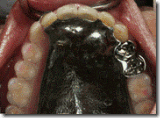

患者A先生

上顎 正面 下顎

患者B小姐

以上兩位患者口內狀況非常複雜,要制定一個好的治療計畫,

不只要考慮到患者的牙齒條件,

還要顧及患者意願、時間、金錢、評估可獲得的結果等等。

所以像這類型的Case 醫師通常在初步的溝通後會先做出一兩個不同的治療計畫,

再和患者解釋,了解患者接受程度。